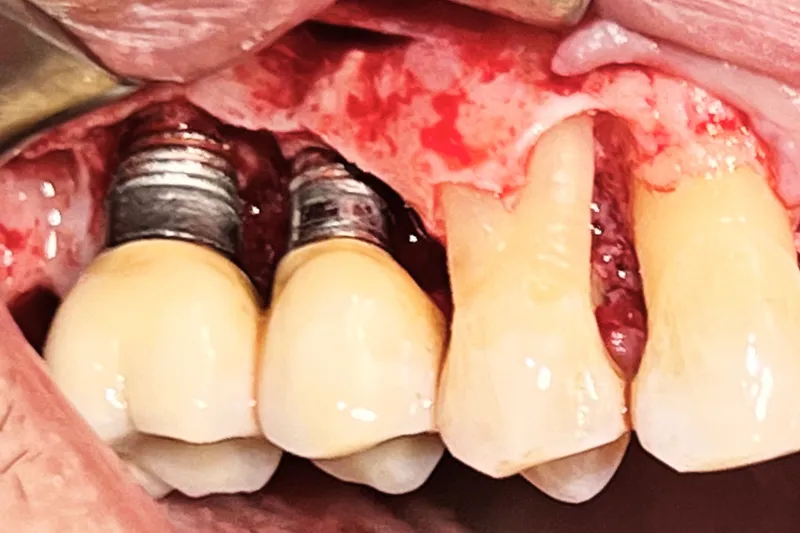

- Periimplantitis skal behandles med parodontalkirurgi i form af lapoperation for at sikre adgang til depuration af implantatoverfladen.

- Intraossøse knogledefekter på ≥ 3 mm er en forudsætning for, at der kan overvejes knogleopbygning ifm. den kirurgiske behandling af periimplantitis.

- Jo smallere defekt og jo flere knoglevægge, jo bedre prognose har den regenerative parodontalkirurgiske behandling af periimplantitis.